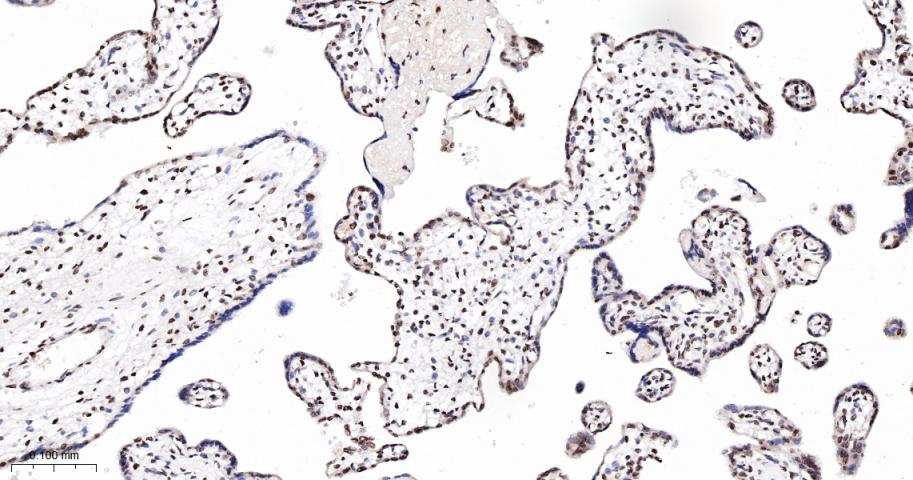

Paraformaldehyde-fixed, paraffin embedded Human Placenta; Antigen retrieval by boiling in sodium citrate buffer (pH6.0) for 15 min; The section was incubated with CDK8 Monoclonal Antibody, Unconjugated (bsm-60609R) at 1:100 overnight at 4°C, followed by conjugation to the bs-0295G-HRP and DAB (C-0010) staining.

Paraformaldehyde-fixed, paraffin embedded Rat Placenta; Antigen retrieval by boiling in sodium citrate buffer (pH6.0) for 15 min; The section was incubated with CDK8 Monoclonal Antibody, Unconjugated (bsm-60609R) at 1:100 overnight at 4°C, followed by conjugation to the bs-0295G-HRP and DAB (C-0010) staining.

Paraformaldehyde-fixed, paraffin embedded Mouse Placenta; Antigen retrieval by boiling in sodium citrate buffer (pH6.0) for 15 min; The section was incubated with CDK8 Monoclonal Antibody, Unconjugated (bsm-60609R) at 1:100 overnight at 4°C, followed by conjugation to the bs-0295G-HRP and DAB (C-0010) staining.